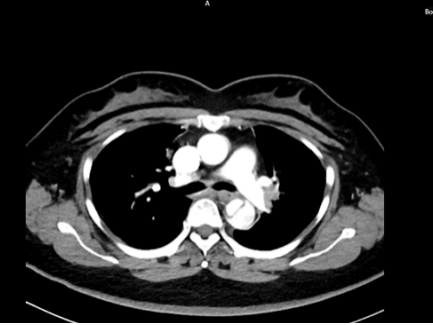

46岁女性患者,因突发胸背部撕裂样疼痛,既往多年高血压病史。

五、主动脉夹层诊断

时间就是生命。医生会结合症状,快速进行以下检查:医院会根据CT血管成像(CTA)进行诊断。如确诊为主动脉夹层,则会进行紧急处理,立即镇痛、控制血压和心率(如静脉注射β受体阻滞剂)。